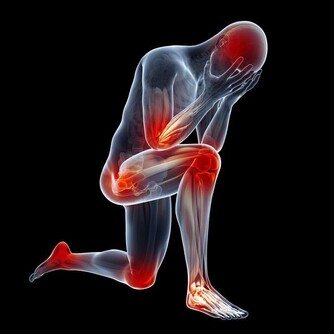

*****4、手抖原因最多*****

手抖的原因很多,有些人在精神緊張、情緒激動或極度疲勞的情況下會出現手抖,一旦這些因素消除,手抖也會隨之消失。而有些人會經常性手抖,吃飯、寫字都會受到影響,這種手抖可能和甲狀腺疾病、帕金森綜合徵、腦神經和上肢神經病變等有關。

如果手抖症狀一直沒有改善,一定要及時求醫、 對症治療。

*****5、手經常麻木*****

腦動脈硬化會減緩神經的傳導速度,

使腦的局部供血、供氧減少,並出現中樞功能障礙,可能引起手麻。

手足麻木還有可能由糖尿病性周圍神經病變引起。

頸椎病同樣可以引起手足麻木。

此外,還有一部分老人由於缺乏B族維生素,會引起末梢神經炎而造成手足麻木。